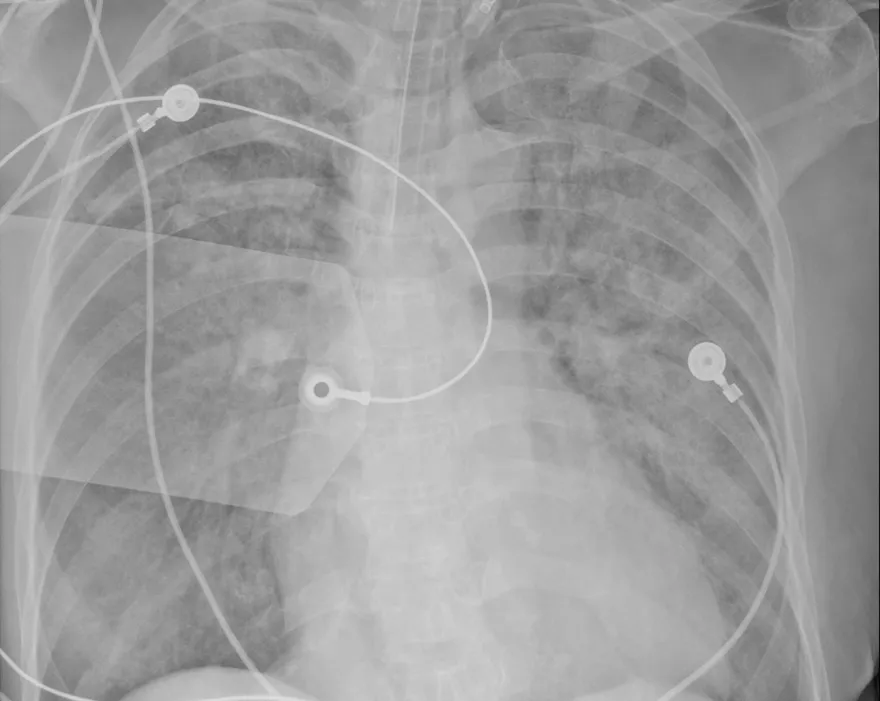

大白肺

嗜睡

咳嗽

全身無力

血氧濃度

肺炎